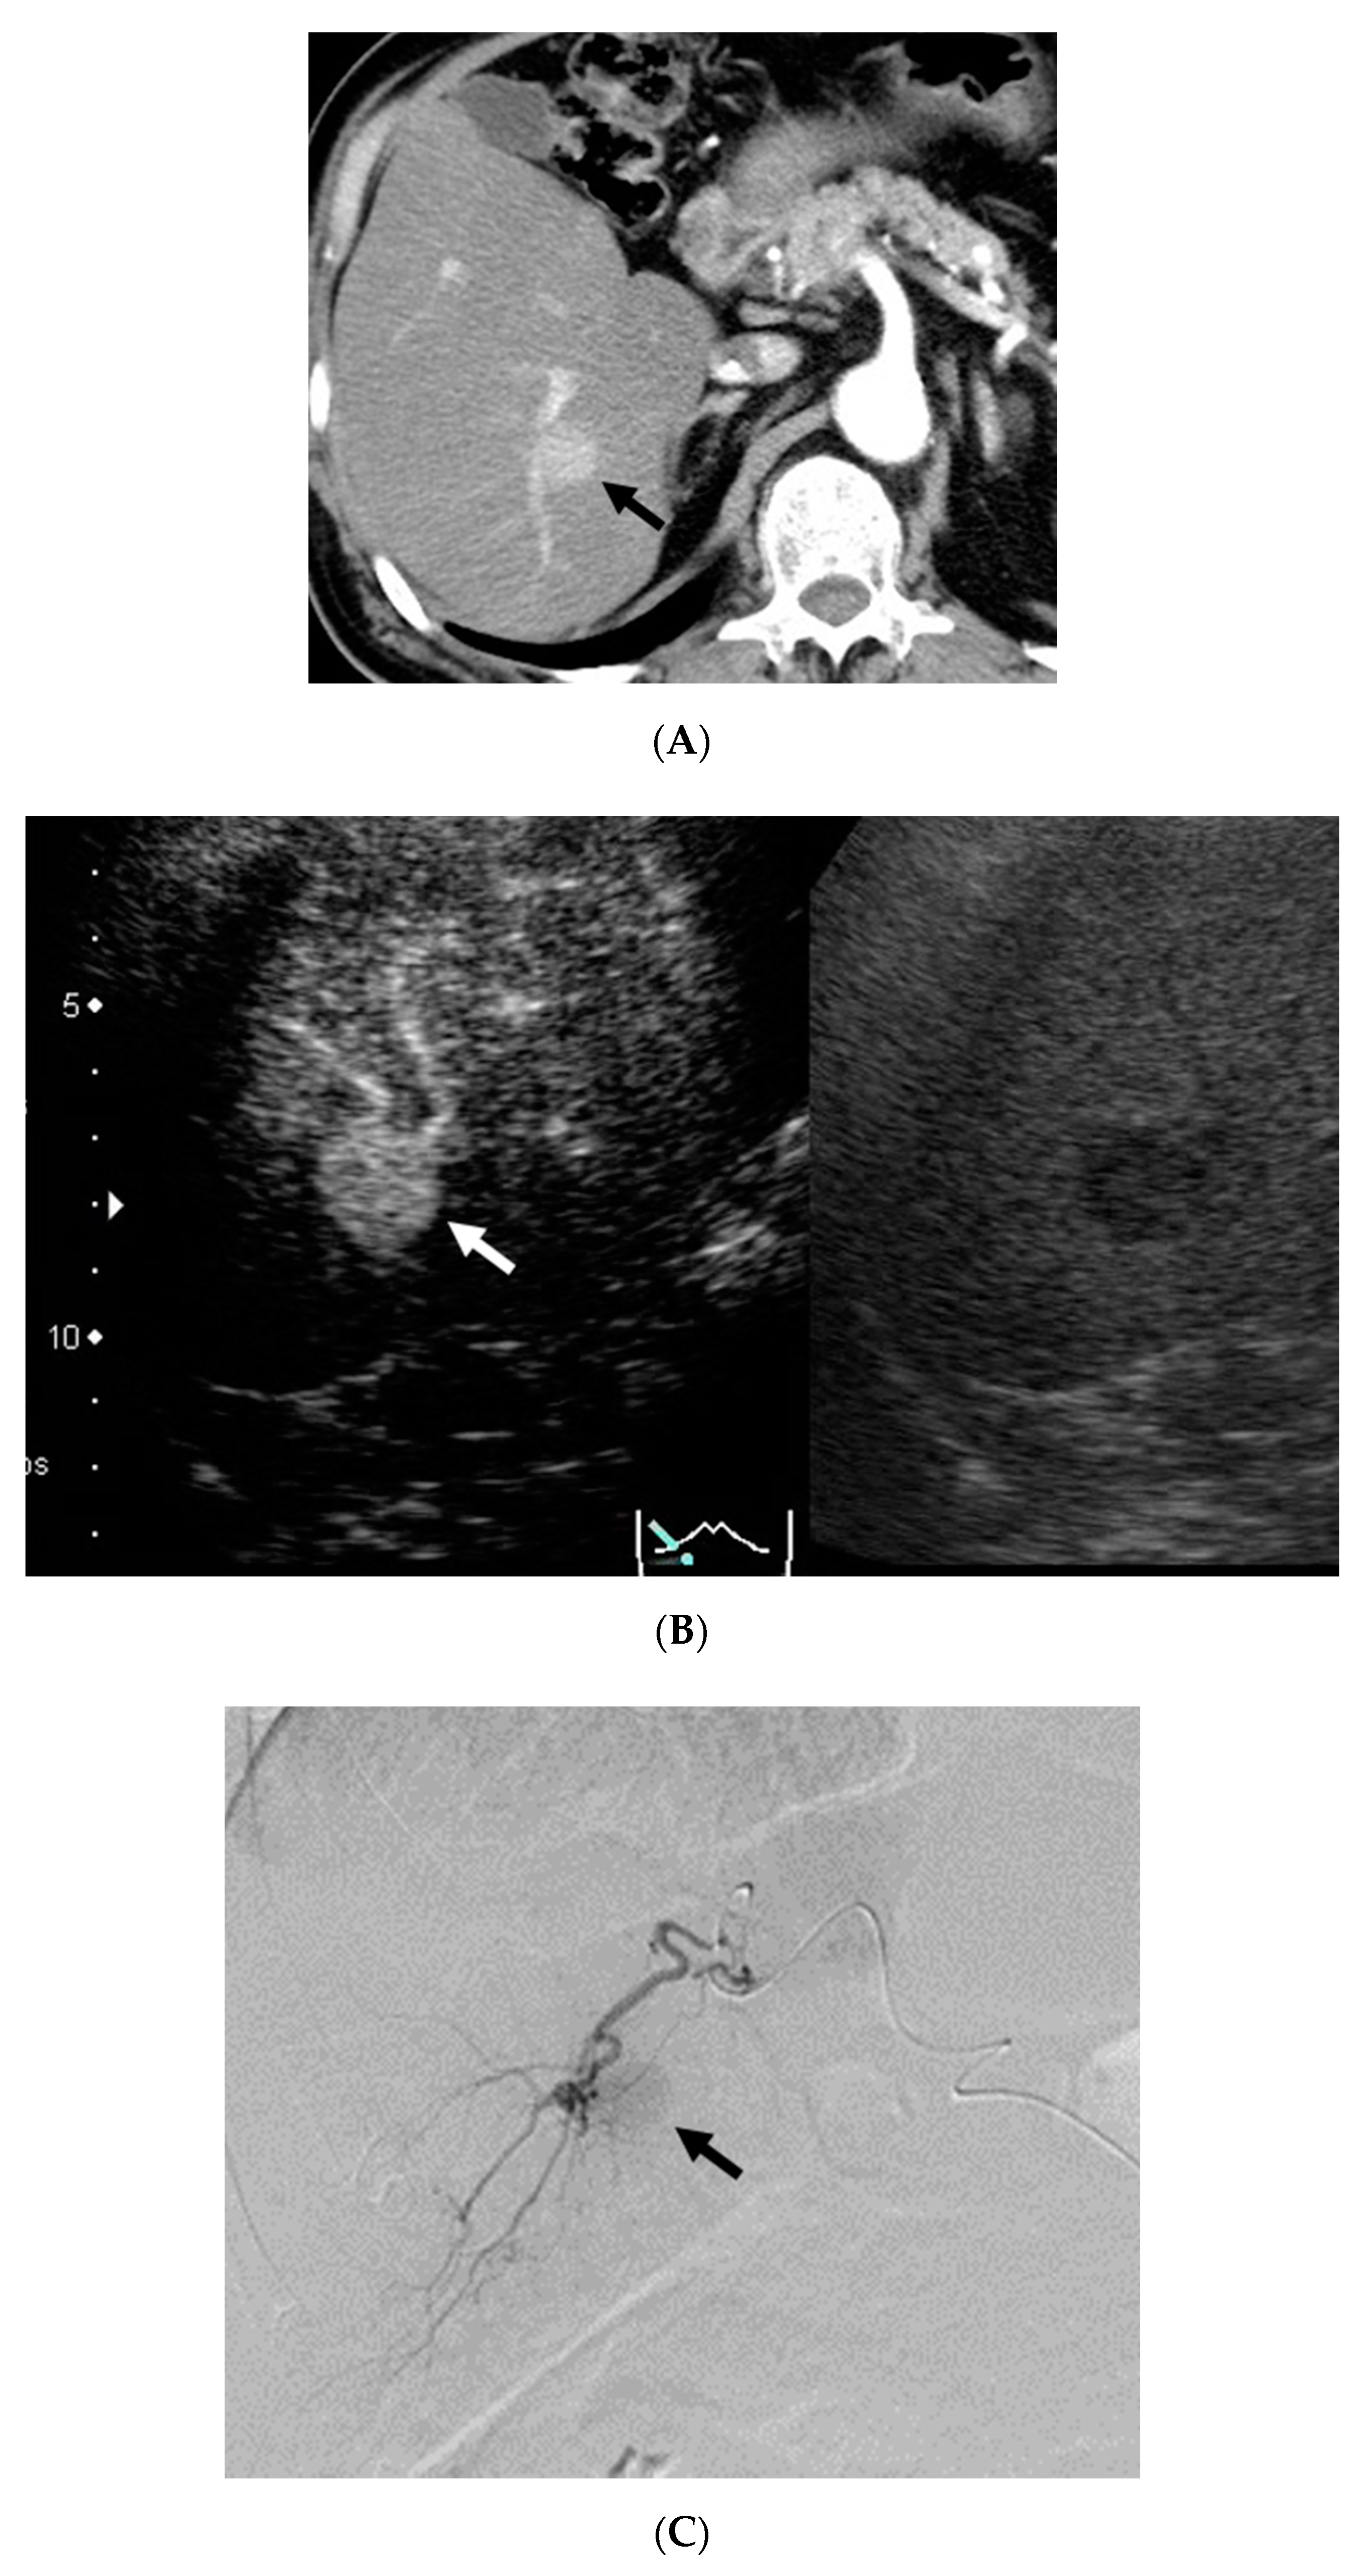

2.2. CEUS Imaging

2.3. CECT Imaging

2.5. Image Analysis